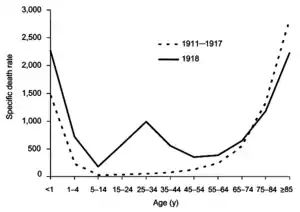

During seasonal epidemics, it is estimated that about 80% of otherwise healthy people who have a cough or sore throat have the flu.[1] Approximately 30–40% of people hospitalized for influenza develop pneumonia, and about 5% of all severe pneumonia cases in hospitals are due to influenza, which is also the most common cause of ARDS in adults. In children, influenza is one of the two most common causes of ARDS, the other being the respiratory syncytial virus.[13] About 3–5% of children each year develop otitis media due to influenza.[8] Adults who develop organ failure from influenza and children who have PIM scores and acute renal failure have higher rates of mortality.[13] During seasonal influenza, mortality is concentrated in the very young and the elderly, whereas during flu pandemics, young adults are often affected at a high rate.[11]

From 1918 to 1920, the Spanish flu pandemic became the most devastating influenza pandemic and one of the deadliest pandemics in history. The pandemic, probably caused by H1N1, likely began in the USA before spreading worldwide by soldiers during and after the First World War. The initial wave in the first half of 1918 was relatively minor and resembled past flu pandemics, but the second wave later that year had a much higher mortality rate,[45] accounting for most deaths. A third wave with lower mortality occurred in many places a few months after the second.[23] By the end of 1920, it is estimated that about a third[11] to half of all people in the world had been infected, with tens of millions of deaths, disproportionately young adults.[45] During the 1918 pandemic, the respiratory route of transmission was clearly identified[23] and influenza was shown to be caused by a "filter passer", not a bacterium, but there remained a lack of agreement about influenza's cause for another decade and research on influenza declined.[54] After the pandemic, H1N1 circulated in humans in seasonal form[1] up until the next pandemic.[54]